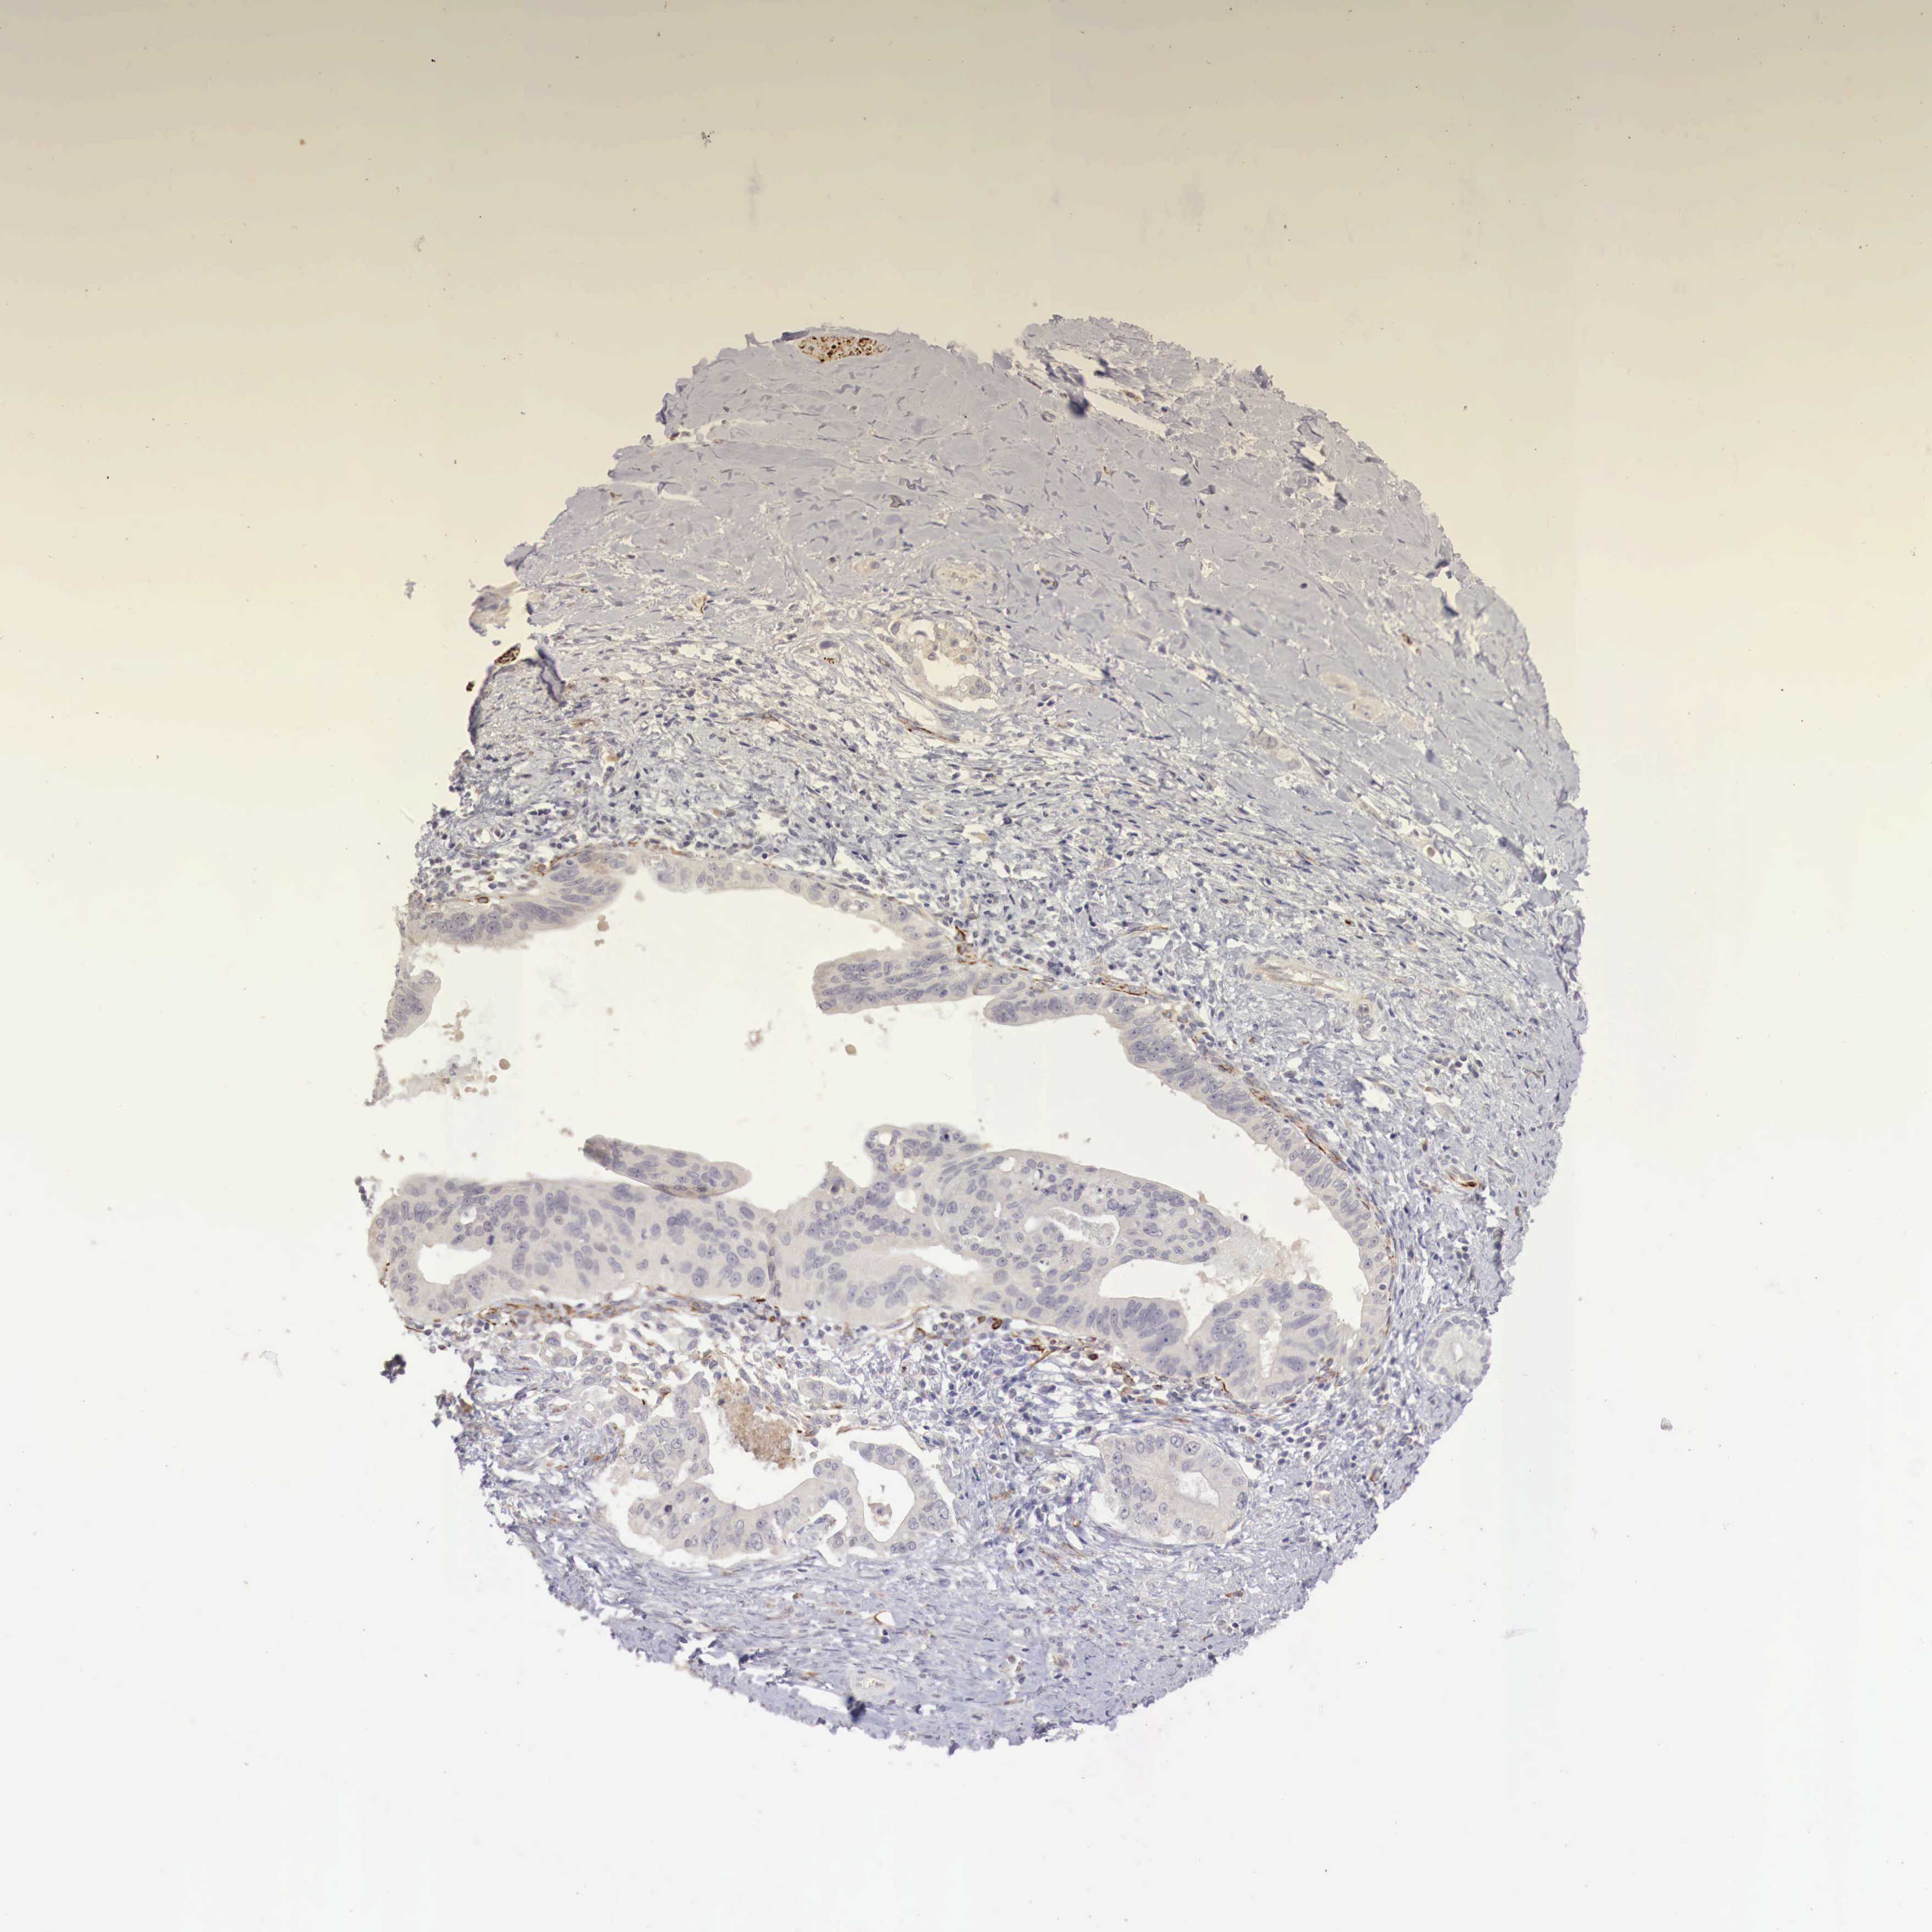

LIVER CANCER - Protein expressioni

A mouse-over function shows sample information and annotation data. Click on an image to view it in a full screen mode. Samples can be filtered based on level of antibody staining by selecting one or several of the following categories: high, medium, low and not detected. The assay and annotation is described here.

Note that samples used for immunohistochemistry by the Human Protein Atlas do not correspond to samples in the TCGA dataset.

Antibody stainingi

Antibody staining in the annotated cell types in the current human tissue is reported as not detected, low, medium, or high, based on conventional immunohistochemistry profiling in selected tissues. This score is based on the combination of the staining intensity and fraction of stained cells.

Each image is clickable and will lead to virtual microscopy that enables deeper exploration of all samples and also displays staining intensity scores, fraction scores and subcellular localization as well as patient and tissue information for each sample.

Antibody CAB000327

Staining

High

Medium

Low

Not detected

Intensity

Strong

Moderate

Weak

Negative

Quantity

>75%

75%-25%

<25%

None

Location

Nuclear

Cytoplasmic/membranous

Cytoplasmic/membranous,nuclear

Carcinoma, Hepatocellular, NOS

Cholangiocarcinoma